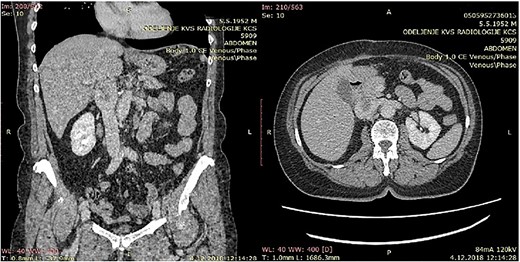

CT of the abdomen that shows a retroperitoneal tumor mass that involves IVC above the renal and under the liver veins.

Because of previous reasons the diagnosis of the primary IVC LMS is often incidental. When symptoms are present, the computerized tomography (CT) or NMR are useful to confirm the presence of a tumor, its pattern of growth, relationship to the surrounding structures, and the presence of caval obstruction [10, 12]. In all five of our cases, MDCT angiography showed tumor of the IVC. The final ultimate diagnosis, of course, is carried out using histopathological and immunohistochemical methods. The pathognomonic findings of LMS are spindle-shaped tumor cells with positive markers for smooth muscle cells, vimentin, muscle actin, alpha-smooth-muscle actin, and desmin [13].